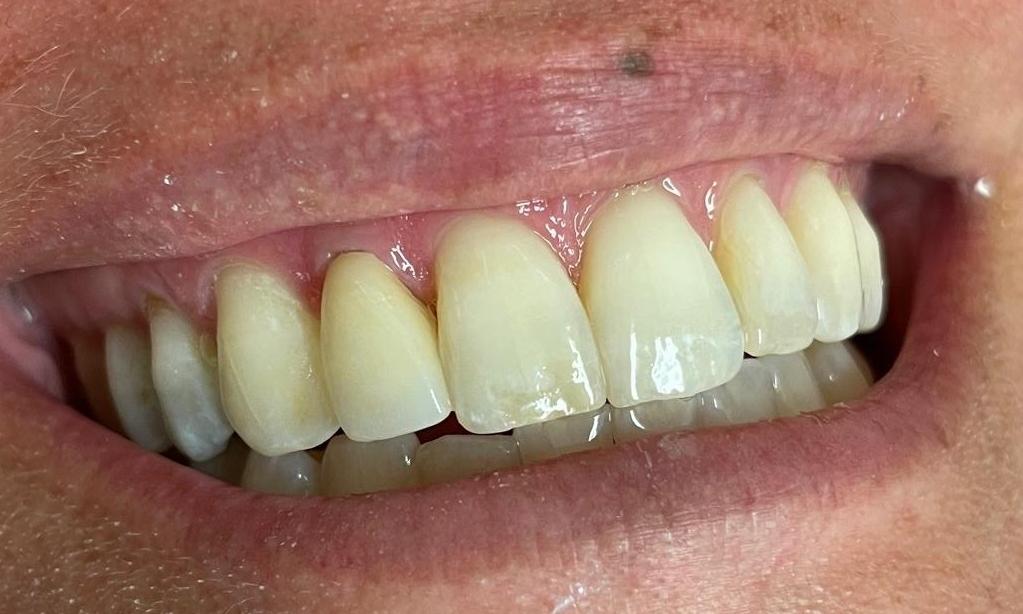

In this case, the patient's tooth #7 had a previous root canal and was darker and did not match the adjacent teeth.  A full coverage all ceramic crown was used to cover the tooth and match the shade to the adjacent teeth